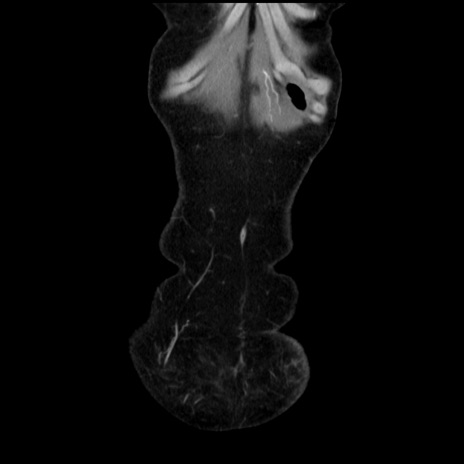

矢状断像

【症例】40歳代 女性

【主訴】上腹部痛、嘔気・嘔吐

【現病歴】約9時間前頃から急に上腹部痛、嘔気、嘔吐が出現。改善しないため救急要請。

【既往歴】子宮頚癌(広汎子宮全摘術、放射線療法)、腸閉塞